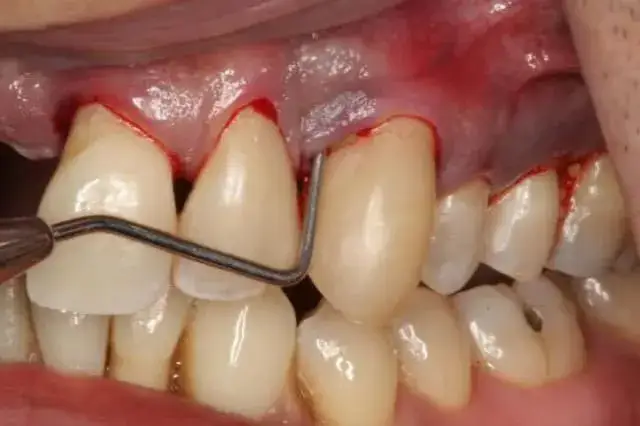

Kobiety w ciąży mogą potrzebować różnych zabiegów stomatologicznych, które są bezpieczne dla ich zdrowia oraz zdrowia dziecka. Wiele procedur, takich jak rutynowe czyszczenie zębów, jest zalecanych i nie stanowi zagrożenia. Ważne jest jednak, aby każda procedura była przeprowadzana przez doświadczonego dentystę, który zna specyfikę opieki nad kobietami w ciąży.- Rutynowe czyszczenie zębów i skaling, które pomagają w usuwaniu płytki nazębnej.